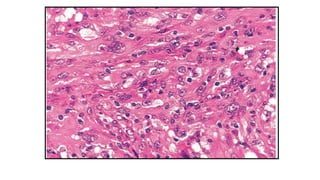

Interdigitating Dendritic Cell Sarcoma

• Neoplastic proliferation of spindle to oval cells with phenoyptic

features similar to those of interdigitating dendritic cells

• Extemely rare neoplasm

• Site :

solitary LN involvement (most common)

Extranodal : skin & soft tissue

IMMUNOPHENOTYPE

POSITIVE NEGATIVE

S100 CD 21, CD35

Vimentin CD1a

Myeloid markers

Cytokeratin

S-100

ULTRASTRUCTURE

• Complex interdigitating cell processes present

• Desmosomes, birbeck granules & lysozymes absent

PROGNOSIS

• The clinical course is generally aggressive, with about half of all

patients dying of the disease

• Commonly affected visceral organs include the liver, spleen,

kidney and lung